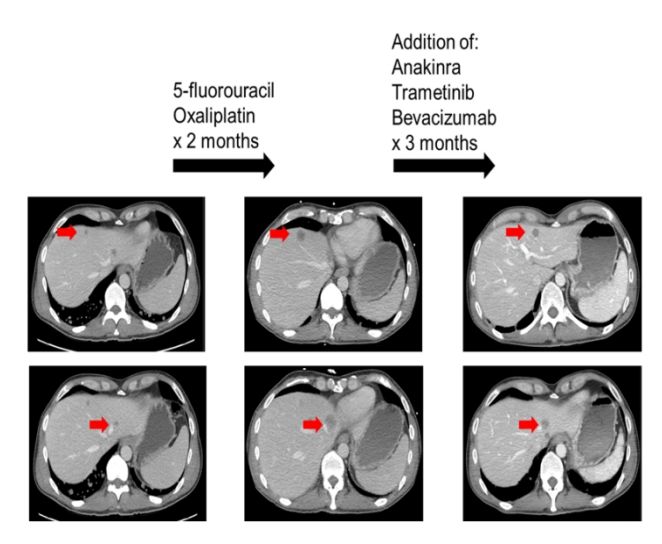

图4患者接受MEK抑制剂及其他靶向治疗案例

因此靶向RAS突变的药物,如MEK抑制剂可能会因大量共突变导致耐药,研究中观察到,RAS突变的多数患者携带的基因共突变可能起到了很重要的致癌作用(图1),因此如要有效的靶向抑制RAS可能需要同时抑制MEK通路及每个患者特异性的共出现的致癌突变。本研究证实,同时应用MEK抑制剂联合靶向匹配的共突变靶向药物可获得33%的客观缓解率,本研究中一例胰腺癌携带KRAS和CDKN2A突变,给予曲美替尼和哌柏西利治疗,部分缓解疗效维持了9个月,该患曾既往接受过含哌柏西利的治疗失败,但当时该方案中未包括MEK抑制剂,提示临床阶段这种治疗方式值得进一步探索。